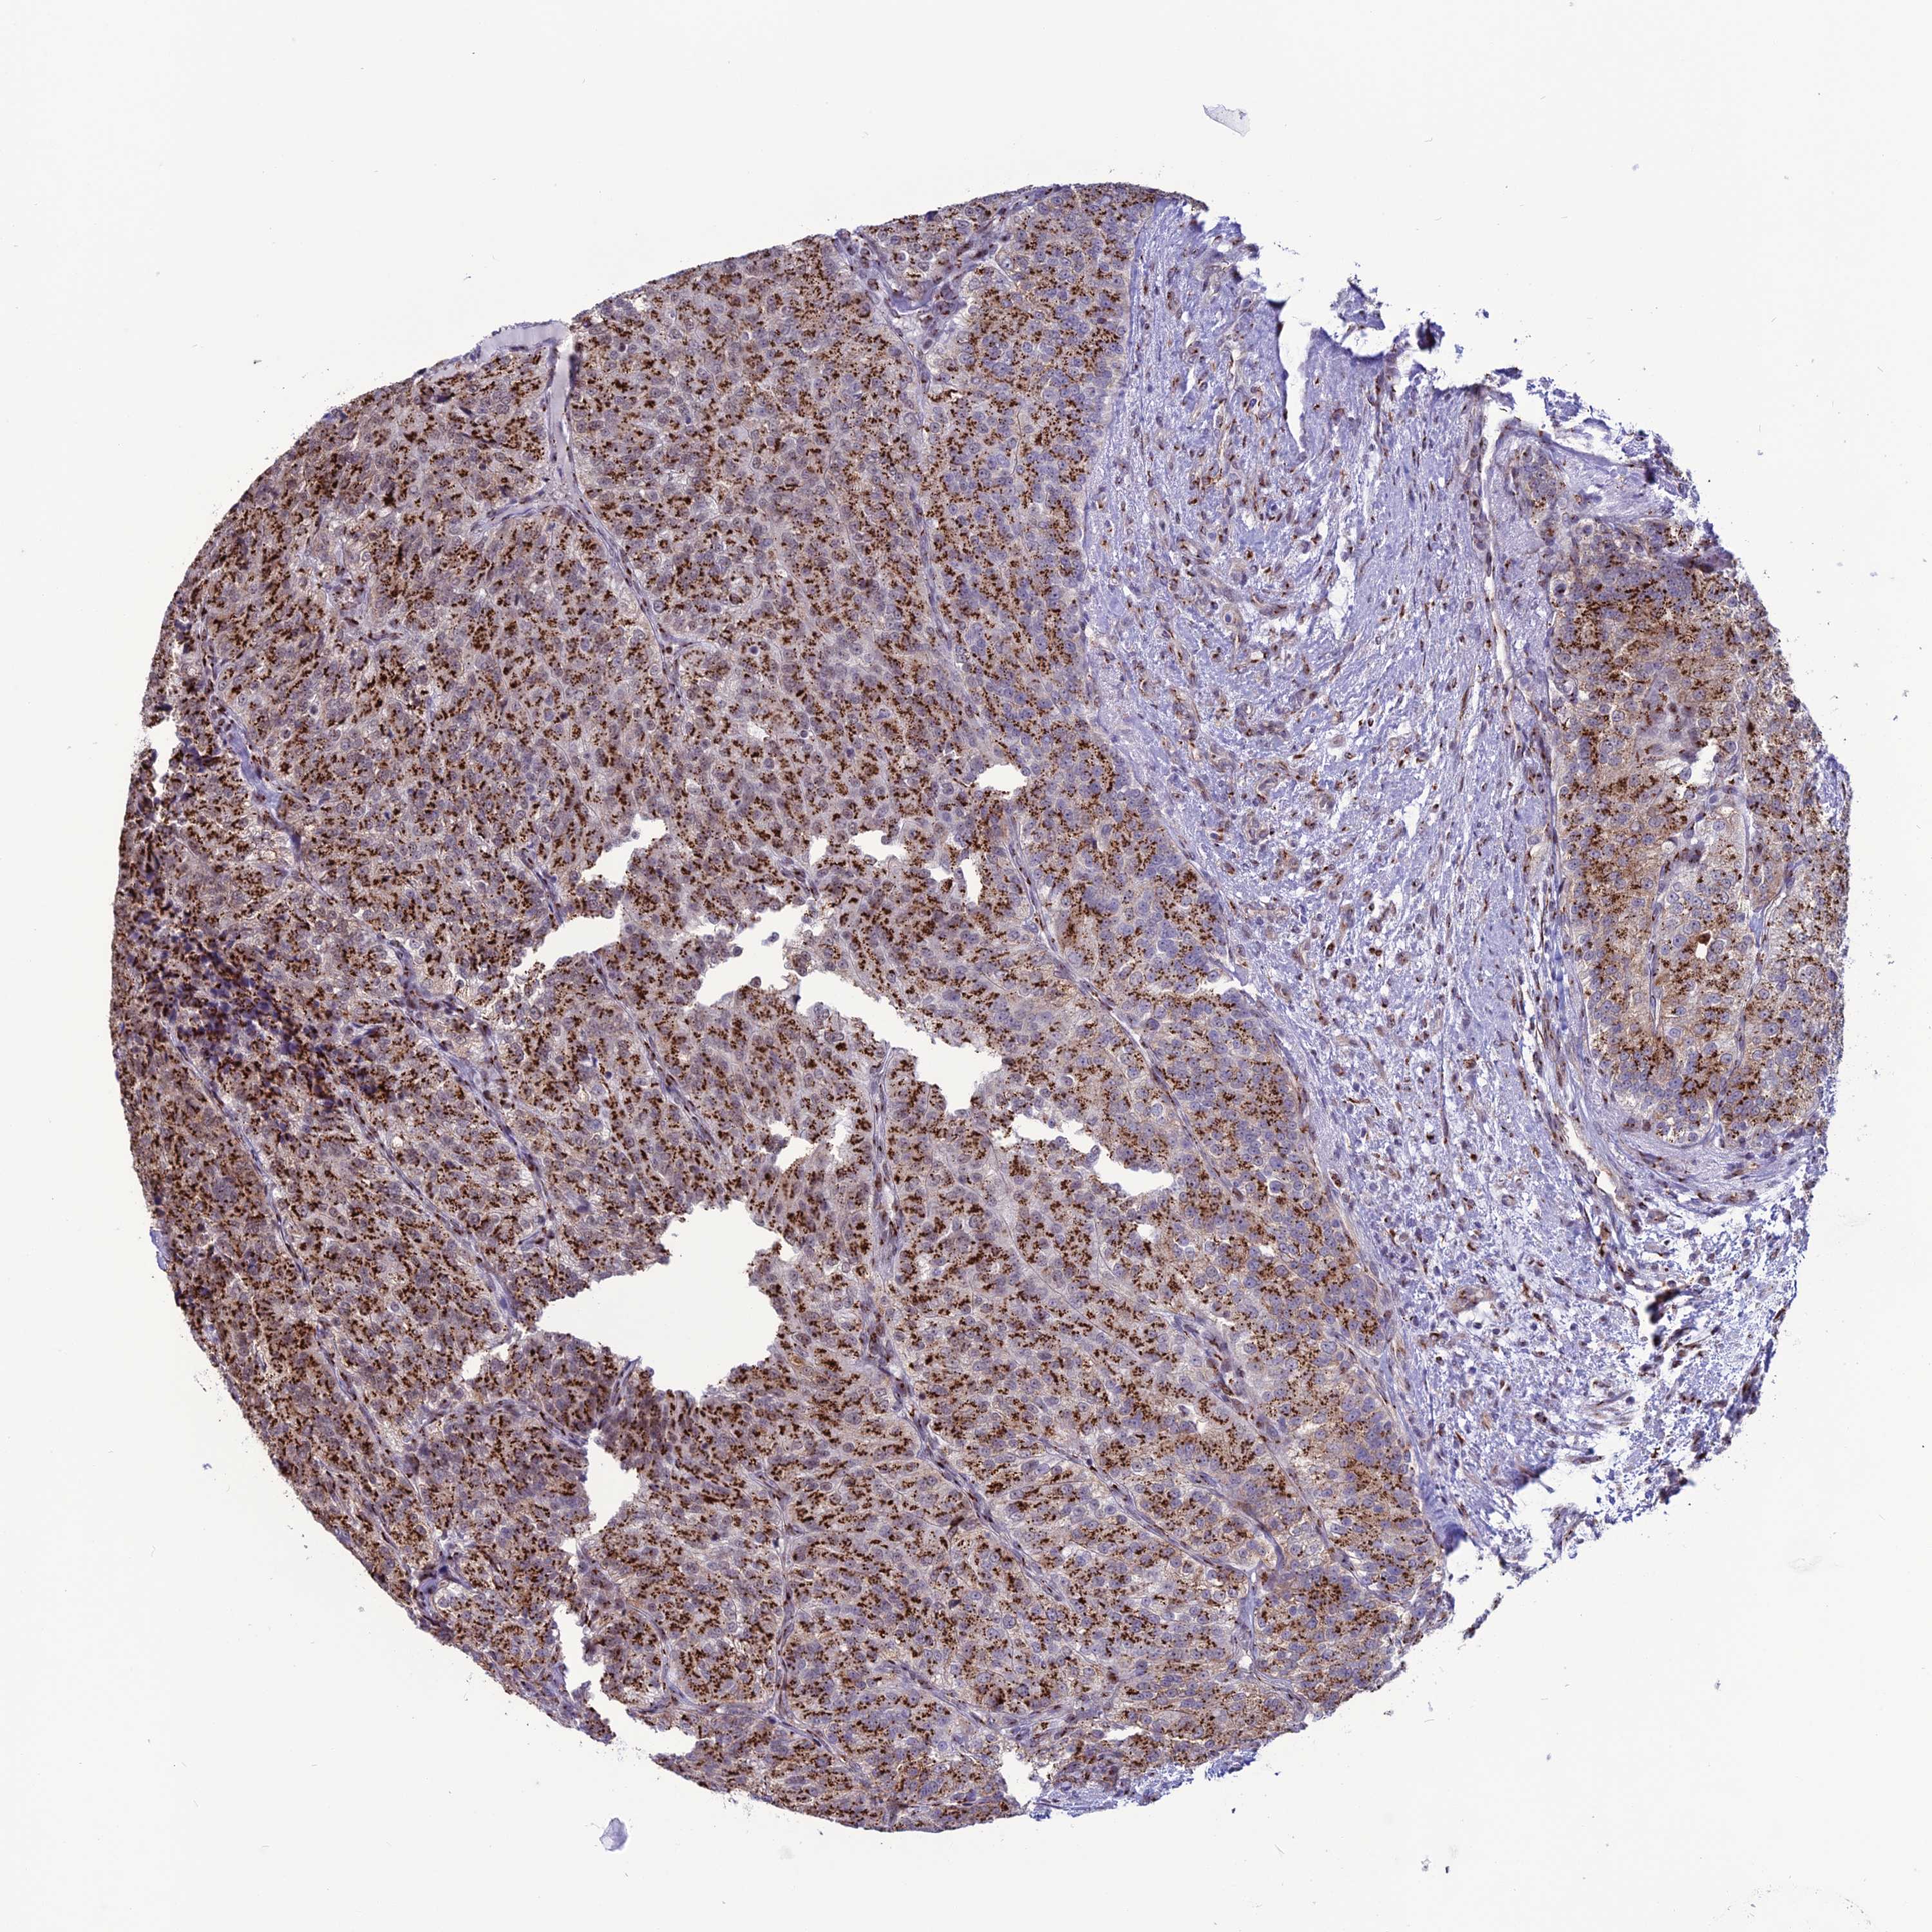

KIDNEY RENAL CLEAR CELL CARCINOMA (VALIDATION) - Interactive survival scatter ploti

The Survival Scatter plot shows the clinical status (i.e. dead or alive) for all individuals in the patient cohort, based on the same data that underlies the corresponding Kaplan-Meier plots. Patients that are alive at last time for follow-up are shown in blue and patients who have died during the study are shown in red.

The x-axis shows the expression levels (FPKM) of the investigated gene in the tumor tissue at the time of diagnosis. The y-axis shows the follow-up time after diagnosis (years). Both axes are complimented with kernel density curves demonstrating the data density over the axes. The top density plot shows the expression levels (FPKM) distribution among dead (red) and alive patients (blue). The right density plot shows the data density of the survived years of dead patients with high and low expression levels respectively, stratified using the cutoff indicated by the vertical dashed line through the Survival Scatter plot. This cutoff is automatically defined based on the FPKM cutoff that minimizes the p-score. The cutoff can be changed by dragging the vertical line or by entering a cutoff value in the square labeled "Current cut-off".

Under the Survival Scatter plot the p-score landscape (black curve; left axis) is shown together with dead median separation (red curve; right axis). Dead median separation is the difference in median mRNA expression between patients who have died with high and low expression, respectively. It is calculated as follows: median FPKM expression of dead patients with high expression - median FPKM expression of dead patients with low expression. This is intended to aid the user in visually exploring custom cutoffs and the associated p-scores and dead median separation.

Individual patient data is displayed and can be filtered by clicking on one or more of the category buttons on the top of the page. Categories describing expression level and patient information include: high, low, alive, dead, female, male and tumor stages. The scale of the x-axis can be toggled between linear and log-scale by clicking on the "x log" button. Mouse-over function shows TCGA ID, patient information and mRNA expression (FPKM) for each patient.

& Survival analysisi

Kaplan-Meier plots summarize results from analysis of correlation between mRNA expression level and patient survival. Patients were divided based on level of expression into one of the two groups "low" (under cut off) or "high" (over cut off). X-axis shows time for survival (years) and y-axis shows the probability of survival, where 1.0 corresponds to 100 percent.

PLEKHA4 is not prognostic in Kidney Renal Clear Cell Carcinoma (validation)

Best expression cut offi

Based on the FPKM value of each gene, patients were classified into two groups and association between prognosis (survival) and gene expression (FPKM) was examined. The best expression cut-off refers the FPKM value that yields maximal difference with regard to survival between the two groups at the lowest log-rank P-value. Best expression cut-off was selected based on survival analysis .

When clicking on this number, the vertical dashed line indicating cut-off, the interactive survival plot, and the Kaplan-Meier curve will be adjusted to show results based on the best expression cut-off.

: 16.71

P scorei

Log-rank P value for Kaplan-Meier plot showing results from analysis of correlation between mRNA expression level and patient survival.

N/A

TCGA RNA samplesi

RNA-seq data is reported as average FPKM (number Fragments Per Kilobase of exon per Million reads), generated by the The Cancer Genome Atlas (TCGA) .

Normal distribution across the dataset is visualized with box plots, shown as median and 25th and 75th percentiles. Points are displayed as outliers if they are above or below 1.5 times the interquartile range. FPKM values of the individual samples are presented next to the box plot.

Average pTPM 22.6

Number of samples 100